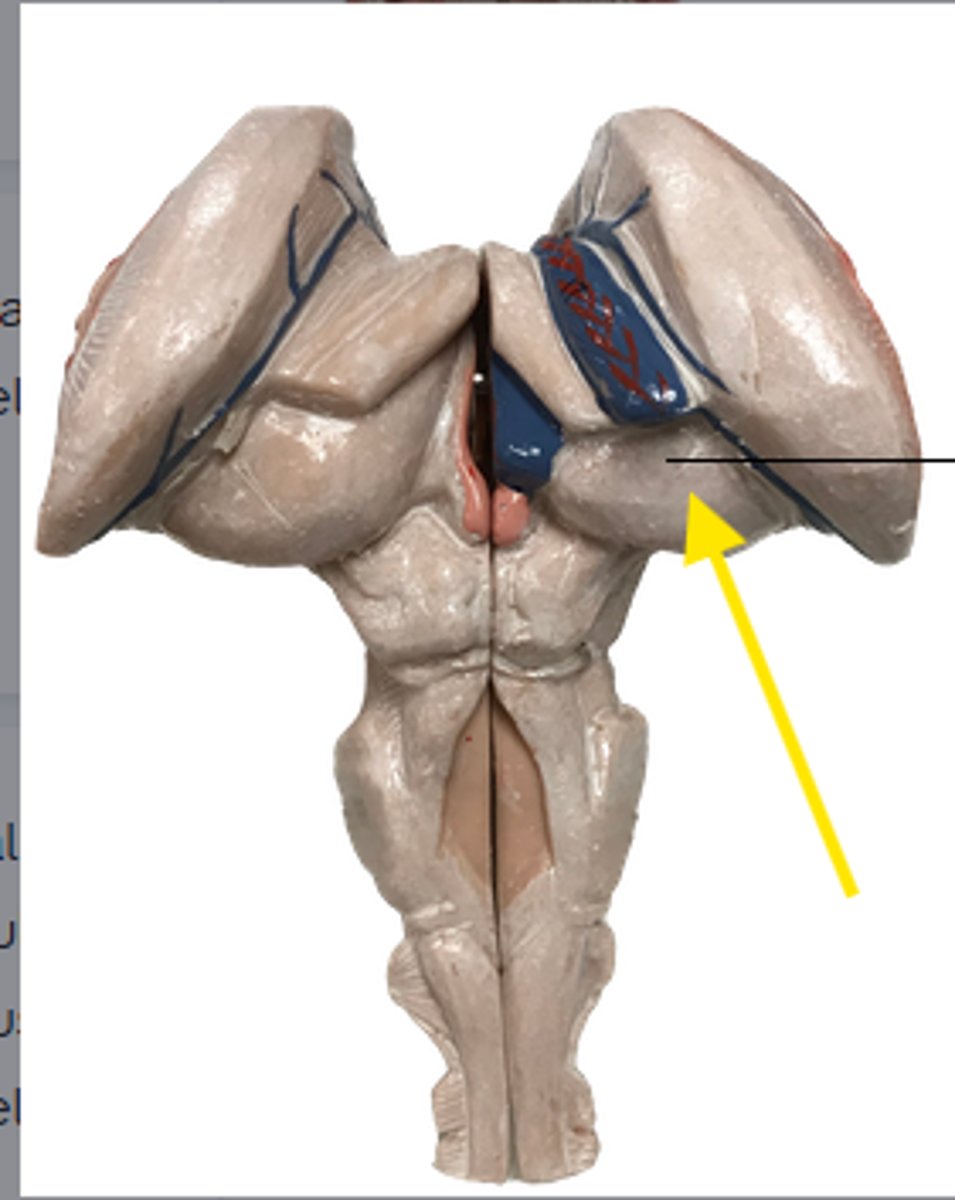

what is the yellow arrow pointing at?

blue arrow is pointing to which structure?

The area the blue arrow is pointing to?

structure blue arrows are pointing to?

What area is the blue arrow pointing to?

Where is the yellow arrow pointing to?